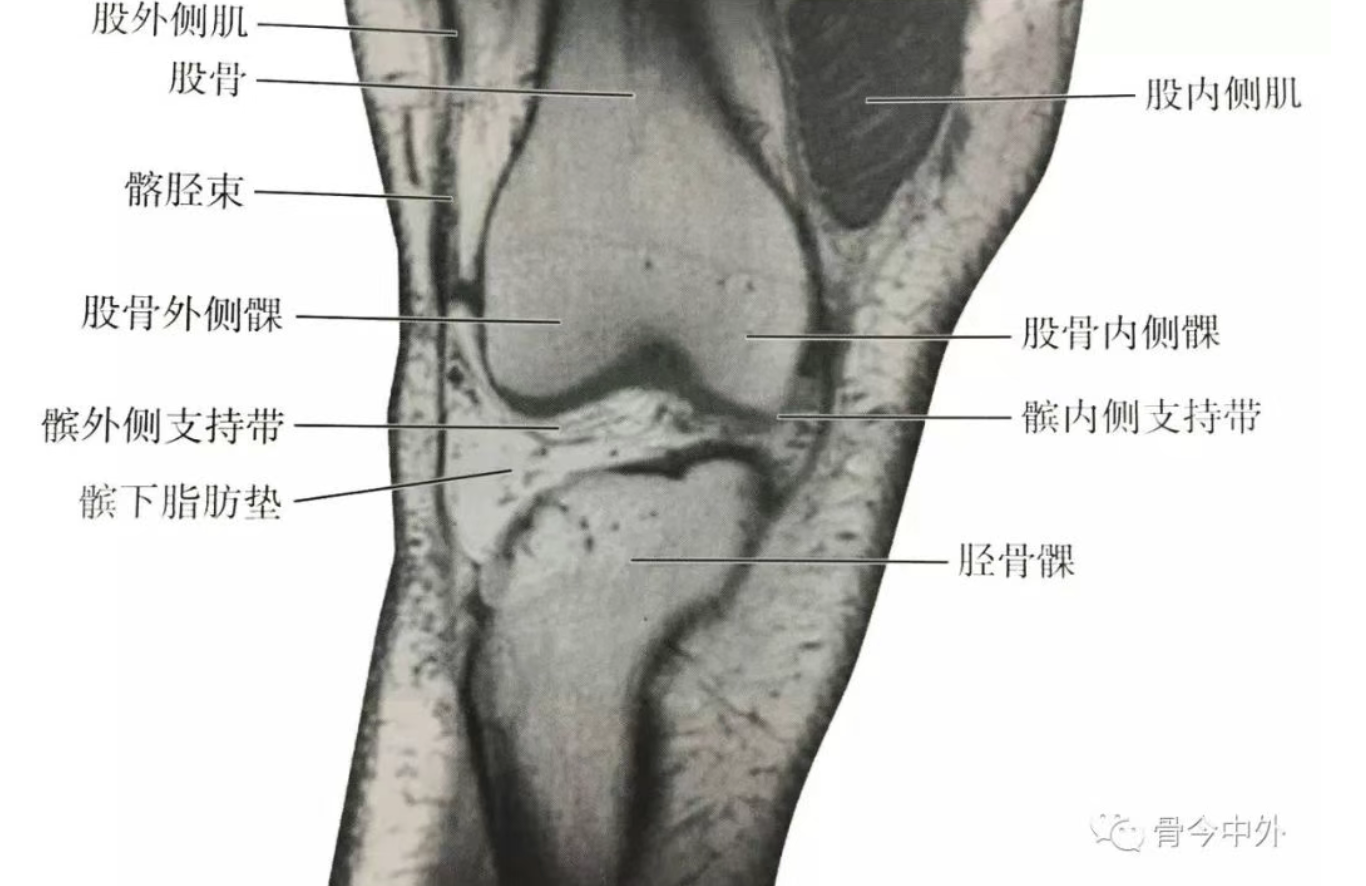

(1)膝前部冠状断层:该层面解剖关系结构如图

膝前部冠状断层

(2)膝中部冠状断层:该层面解剖关系结构如图

膝中部冠状断层